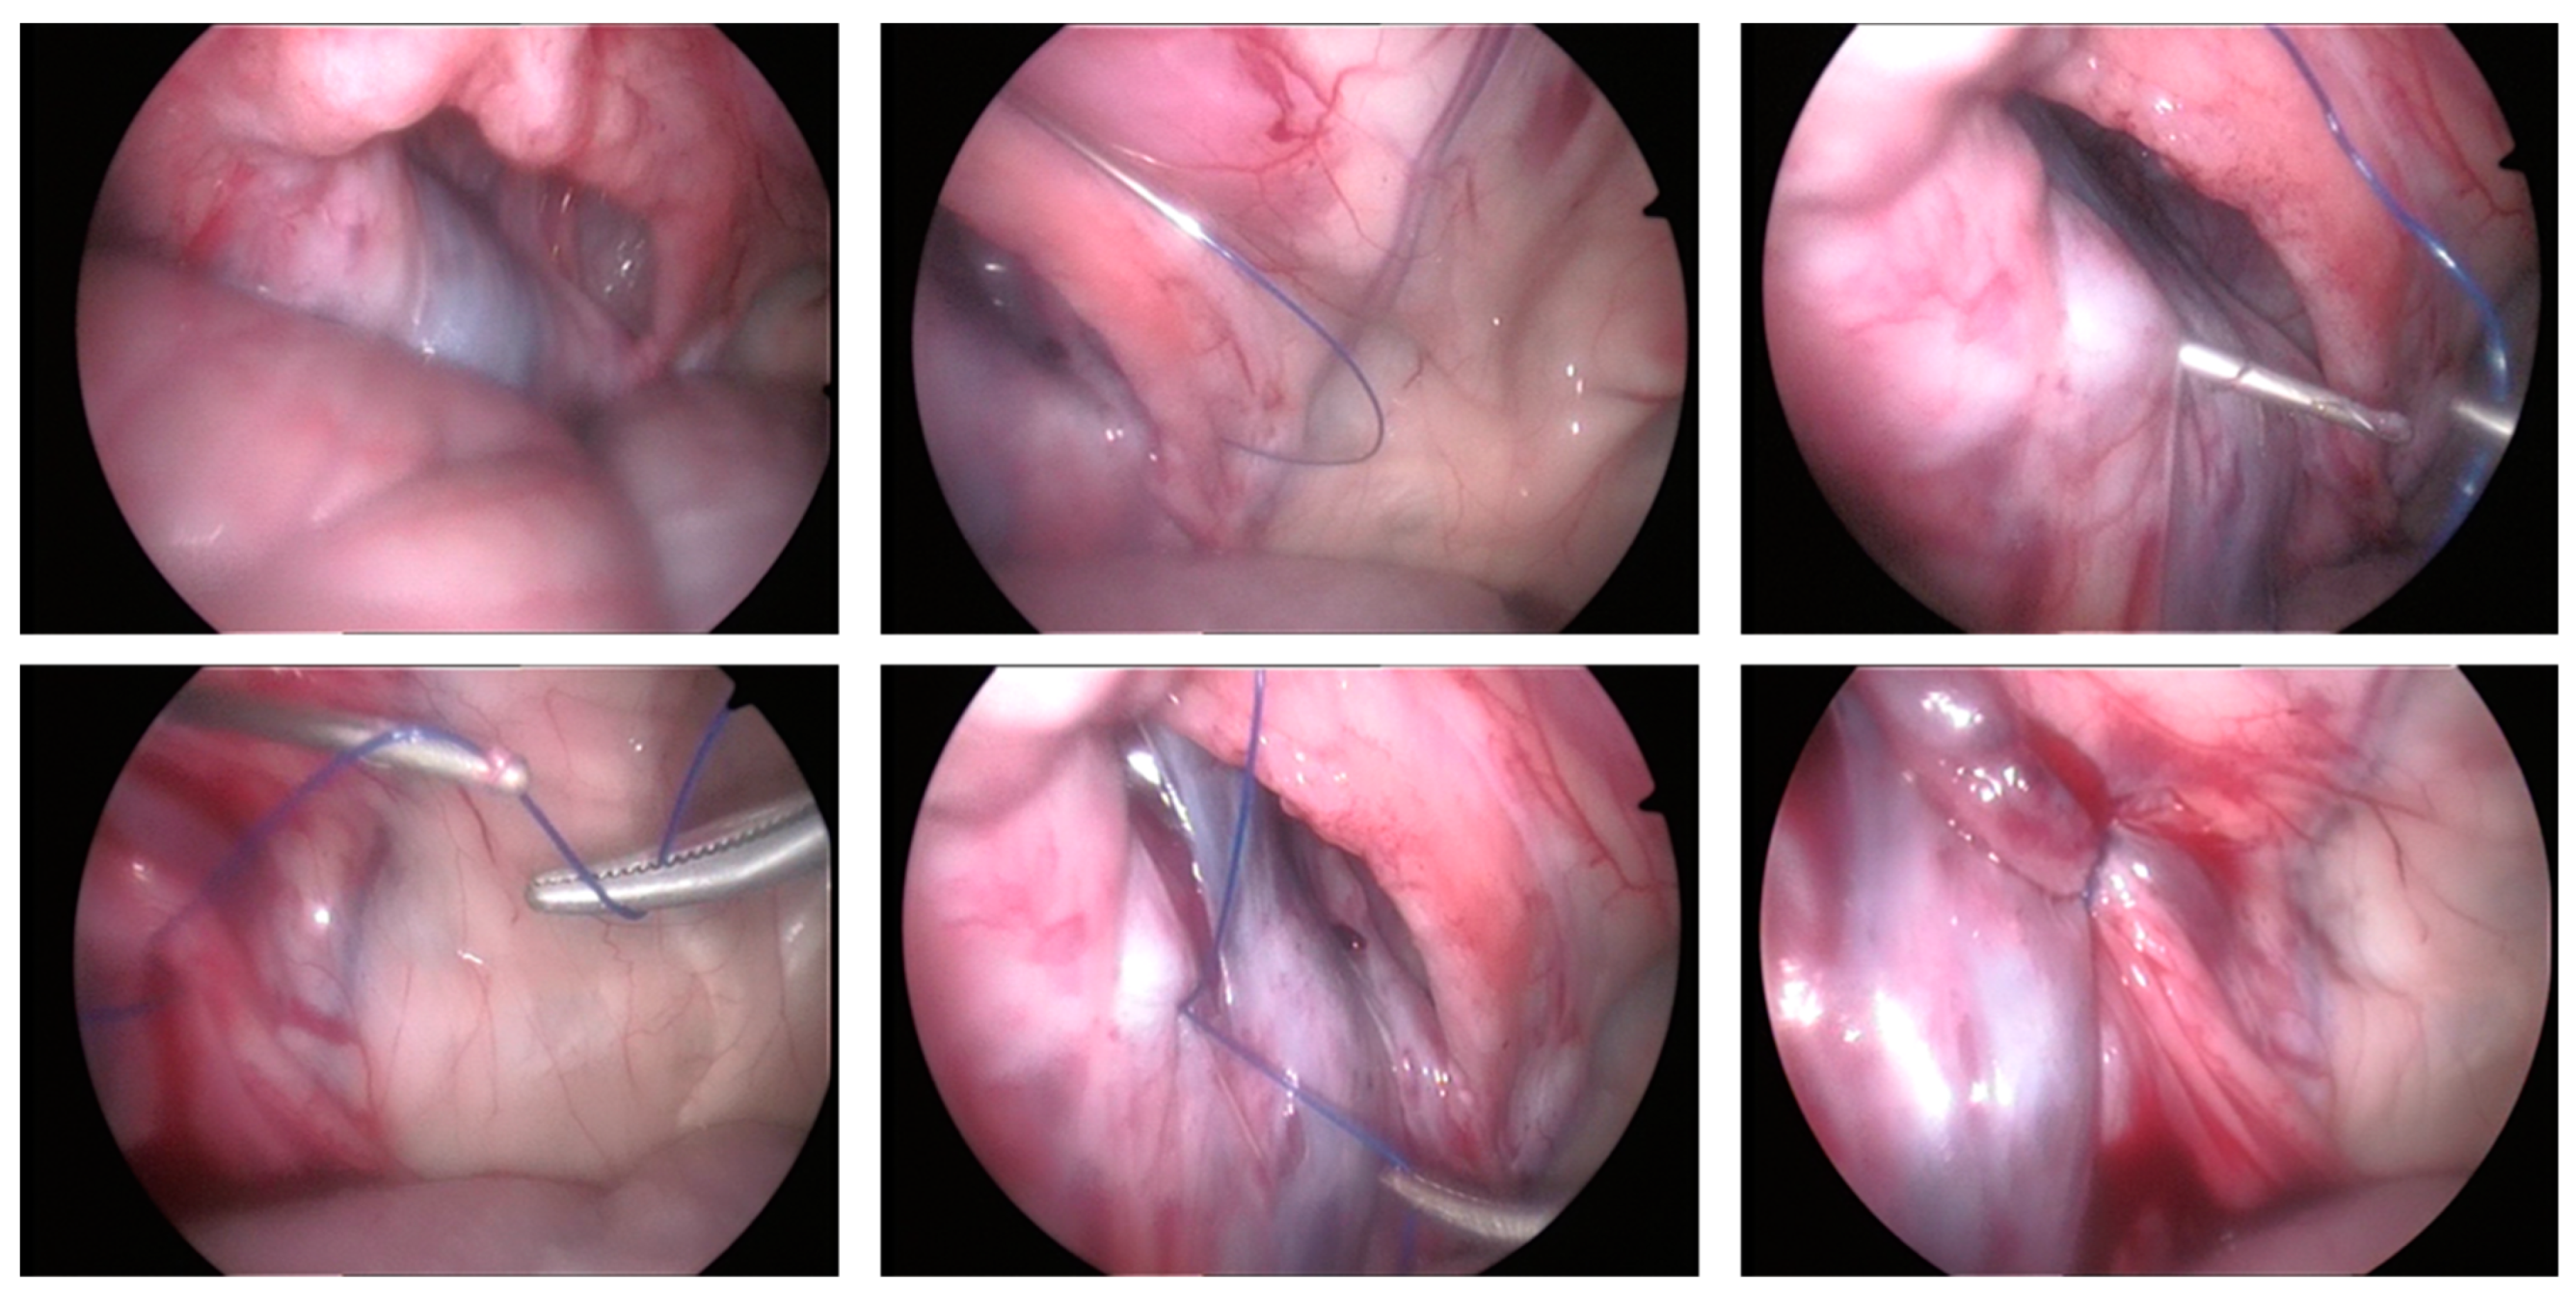

2.1.2. LAPS Surgical Procedure

2.1.3. Assessment of IIR Partial Closure

3.2. Clinical Cases